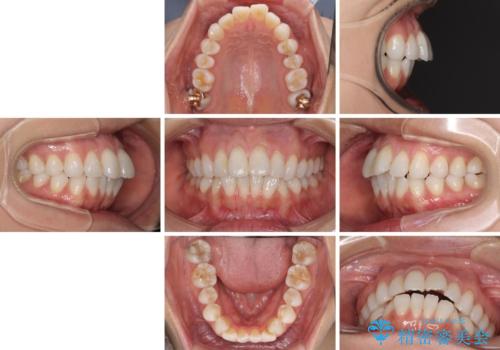

少しだけ飛び出た前歯を整えたい インビザラインによる矯正治療

- インビザライン

- 1年6ヶ月

- 少しだけ前に飛び出ている前歯を気にして来院された患者様です。

上顎歯列全体を後方に移動させる必要があり、インビザライン単体での治療は困難と判断し、補助装置により左右側方歯列を移動させた後にインビザラインを用いることとしました。

インビザライン単独でも上顎歯列全体を後方移動することで臼歯の咬み合わせを改善できる場合もあります。しかしながら、矯正治療は当初設定したゴールに到達する必要があり、今回のような場合ではインビザライン単独では達成の可能性が低くなるので、補助装置を使用して、より確実に治療を行うこととしています。